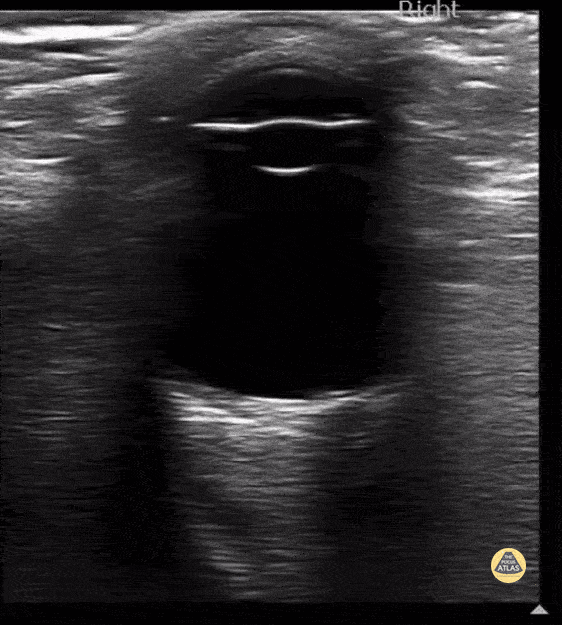

Peds-Orbital - Normal Eye

Normal ocular anatomy, note the cornea, iris and lens anteriorly Contributor: Maher M. Abulfaraj, MD, @mahermabulfaraj